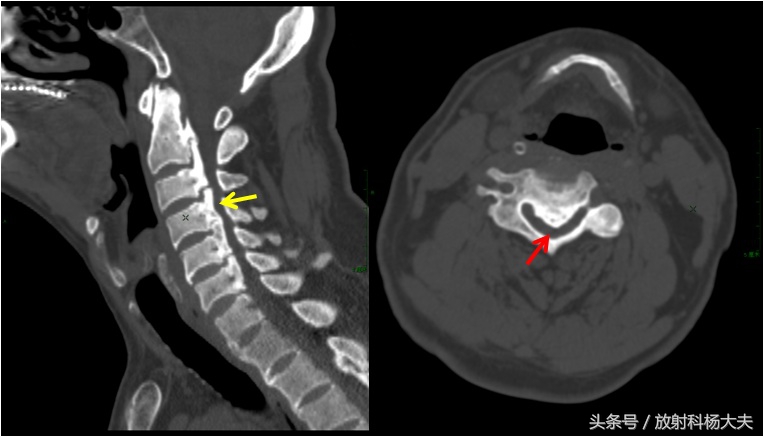

后纵韧带骨化在沿着纵轴方向生长的同时,在水平方向也同时扩大,形成椎管内的占位性病变,使椎管容积变小、椎管狭窄,造成脊髓、神经根受压,脊髓被挤压呈月牙形状,并被推向椎管后壁,骨化块的后壁呈波浪状改变。骨化块主要由板层骨构成,由椎体后缘至板层骨之间依次为纤维组织、纤维软骨、钙化软骨。骨化灶与硬脊膜粘连,随着压迫程度的增加,硬脊膜变薄甚至消失,有时硬脊膜也发生骨化。由于骨化块不断增大,脊髓受压发生严重变形,神经组织充血水肿,脊髓前角细胞数量减少,形态缩小。脊髓臼质有广泛的脱髓鞘变。

CT图,左图黄箭为后纵韧带骨化,右图红箭为椎管,严重狭窄

有时候轻度的OPLL在普通X线片上不容易被发现,此时CT具有很好的确诊价值,对病变范围,程度显示的更佳清晰,利于术前指导。